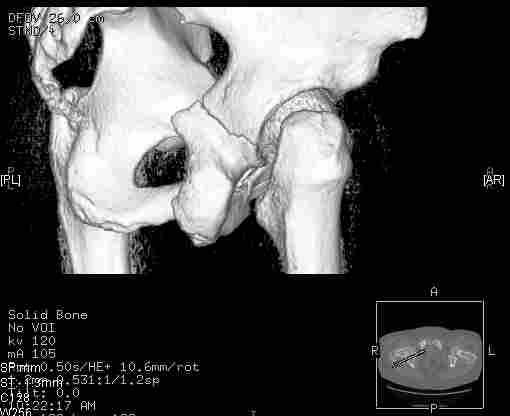

Удалось сегодня вывести пациентку в соседнюю больницу, где есть кт. Срезы сделаны только горизонтальные.

Следом 3d